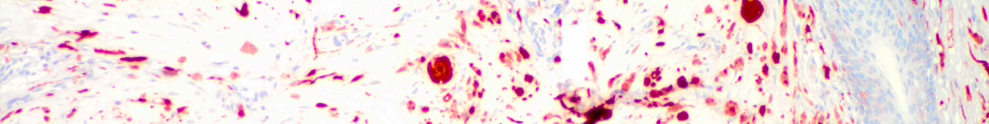

Die immunhistologische bzw. -zytologische Untersuchung hat die Aufgabe, antigene Strukturen in Gewebeschnitten oder in einzelnen Zellen zu erkennen. Dazu stehen eine Vielzahl von Antikörpern zur Verfügung, die auf das Zell- und Gewebsmaterial aufgebracht werden. Bei positivem Ausfall erfolgt eine Antigen-Antikörperreaktion. Das Reaktionsprodukt kann dann in nachfolgenden Reaktionsschritten mit gekoppelten Farbstoffen sichtbar gemacht werden.

Die Ergebnissse immunhistologischer Untersuchungen sind vor allem bei der Klassifizierung verschiedener Tumorerkrankungen und deren Vorstadien bedeutsam.

Melanommetastase (Melan A)